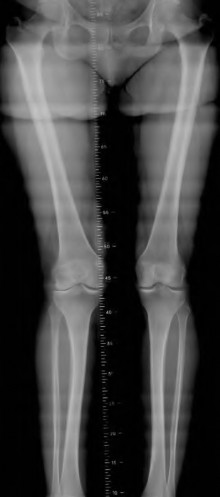

A 45-year-old female with developmental dysplasia of the hip (DDH) presents for THA. Preoperative radiographs show the femoral head is subluxated, with 80% proximal migration relative to the height of the normal true acetabulum. Based on the Crowe classification, what type of dysplasia does she have?

Explanation